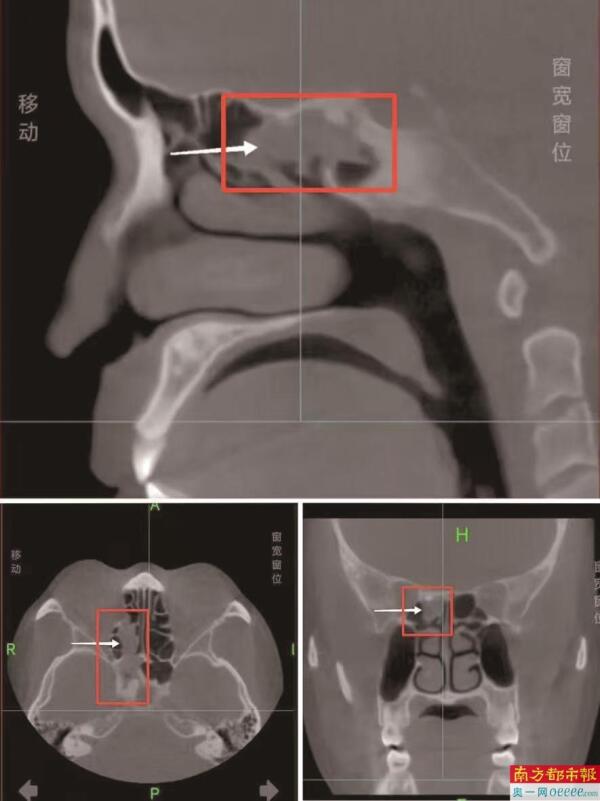

阿杰的CT影像显示。

CT结果显示:阿杰的右侧蝶窦存在占位性病变。存在一个性质待查的“骨瘤”,并同时诊断出右上颌窦囊肿、右侧筛窦、蝶窦炎、鼻中隔偏曲及鼻炎。唐医生告诉阿杰,蝶窦内的这个“异物”不一定是骨瘤,也可能是其他东西,但无论是什么,想彻底解决问题,必须通过手术探查清楚。同时,长期的异物存在已导致局部炎症和反复头痛。考虑到多年饱受困扰,阿杰选择了手术。

唐志元副主任医师介绍,鼻窦(尤其是位置深在的后组筛窦、蝶窦)异物在临床上并不常见,且非常隐蔽,极易被误诊为慢性鼻窦炎、鼻窦囊肿甚至肿瘤,长期、顽固性鼻窦炎患者应提高警惕。像阿杰这样,异物存留时间如此之长、体积如此之大(3厘米),且反复引起感染的情况更为罕见。精准的影像学评估(如针对性强的CT扫描)和医生基于经验的准确解读是诊断的关键。唐医生也提醒阿杰,术后仍需密切随访观察,长期慢性炎症和手术本身可能对鼻腔鼻窦黏膜造成一定影响。